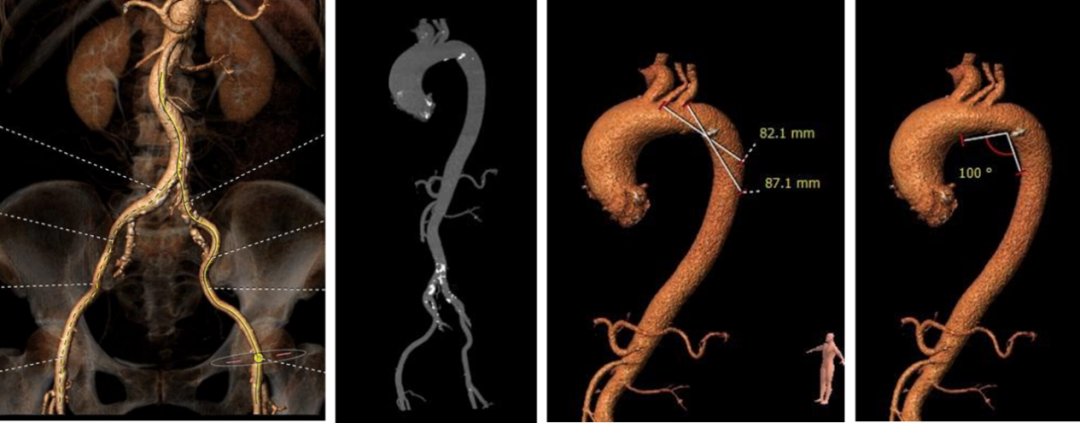

• 主动脉瓣环与水平面夹角近70°,横位心,主动脉弓角度与宽度可

• 入路血管散在钙化,双侧血管内径良好,整体入路血管条件良好

• 瓣环平面水平夹角较大,主动脉弓部夹角与弓距可,预估输送系统可顺利过弓,跨瓣难度增高,必要时备Snare辅助 。

• 推荐右侧股动脉为主入路,左侧辅助入路,推荐20F血管鞘。

• 根据当前影像资料及测量数据,推荐跨瓣角度为LAO 13° CAU 8°(右窦中心位)左右。

• 推荐使用22mm球囊预扩张,推荐球囊预扩角度为LAO 21° CRA19° (左冠切线位)左右,推荐预装AV26瓣膜。

• 释放角度推荐LAO 4° CAU 35°(左右重合)左右,释放高度推荐较高位(瓣环下0- 2mm)。释放后建议调整至左前斜头位( LAO 21° CRA19°)进一步确定人工瓣膜形态。